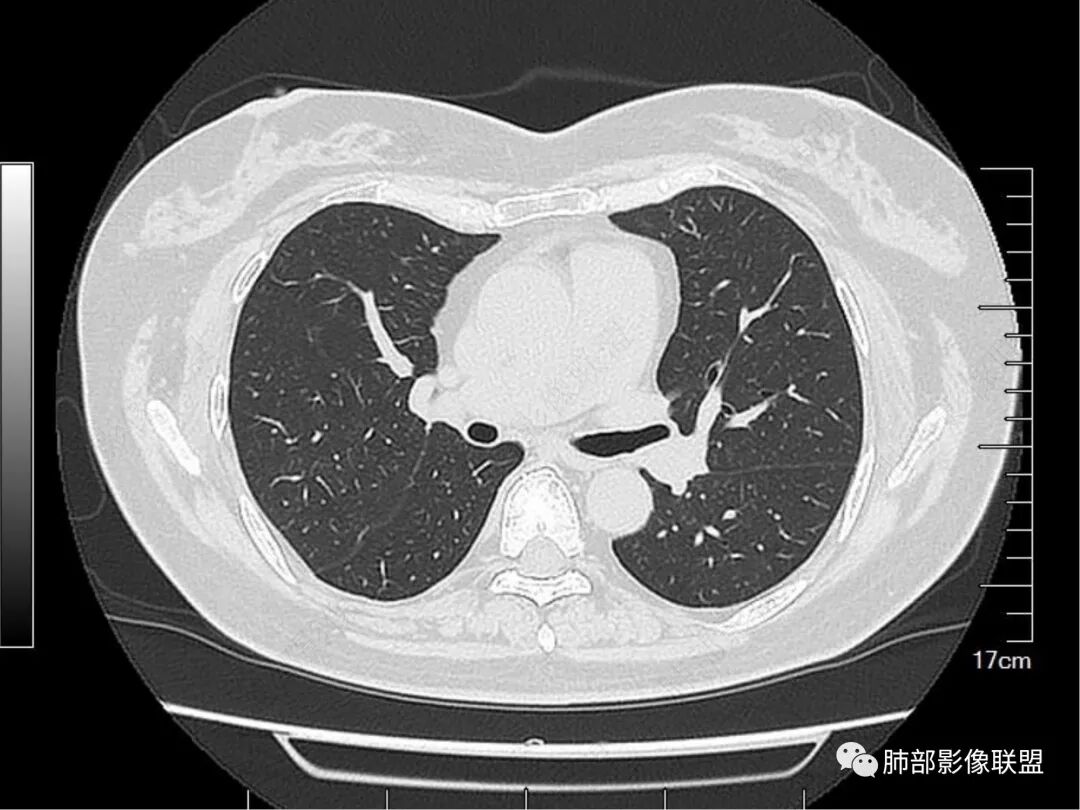

1. 病史简单,老年女性,体检发现肺结节,1年后复查病灶可疑稍增大。

2. 首先定位。这个病变位于胸膜下、肺内病变没问题。请仔细看箭头所示的条索影,我感觉像小叶间隔。

伪影太重了。仔细看,这里是两个支气管分支。而且倾向于小支气管或细支气管水平

继续看。病变的偏远端依然有支气管通行。

病变的定位,是次级肺小叶内,包绕小叶中心结构,并且有一部分病变是局限于一个腺泡结构的,也就是Reid'S小叶;

我们先分析支气管。刚才的截图是明确可以看到支气管显示的。那么它是扩张吗?

再来。注意看病灶下缘的这个支气管,这里几乎没有病灶了。与周围临近的支气管相比。

所以,这些支气管显影,大概率不是牵拉支扩,而是肺泡填充以后的支气管显影。当然,可能存在轻微的支气管扩张。但是,已经不是病变的主要因素。后面还有证据支持。

看完支气管我们继续看这个次级肺小叶的背景。

这里几乎是病灶的最上缘。明显是有丝丝拉拉的不干净的背景,与周围正常组织比较,很明确。

较中央的区域。明确的细网格,多发的。

这个细网格可以是什么引起呢?

1.血管因素,增粗的血管可以;

2.淋巴道因素,比如淋巴瘤、反应性淋巴增生;

3.结缔组织的内容增多,比如免疫性疾病相关造成的黏多糖或者什么复合物增多,或者是什么纤维增多;

4.很重要的一点,就是肺泡塌陷。邻近这种“隔”的肺泡塌陷,加上原有“隔”的背景,形成了这种增粗的表现。

那么这个病变,倾向于哪个原因引起的呢?我们暂存。后面还有证据。

请大家仔细观察这个条索,与胸膜相连,局部结节感。这个大概率是小叶间小静脉的走行。

这里有个特点,是偏侧的,不是reid's小叶 的一圈“隔”都增厚,是局限性的。这种增厚,什么原因可以引起呢?比如:血管的问题,里面有肿瘤。比如淋巴道的问题,有癌淋,或者有间质纤维的不规则增生。

当然,淋巴道的感染也可以,比如结核。非感染性因素也可以,比如结节病。

请仔细观察病灶周围情况,比如临近血管、临近胸膜。有个特点,胸膜牵拉并不明显,邻近血管走行还算正常。

这里,可以佐证了。假如支气管扩张是收缩力引起的,而且支气管扩张如此明显,它周围的组织不会一丁点表现没有,离胸膜如此的近,竟然一点牵拉的意思都没有。

总结一下病变表现:病变区肺小叶背景不干净。整体位于单个次级肺小叶内,围绕小叶中心结构,部分局限于reid小叶的病变。支气管的显影,是肺泡填充为主要因素,收缩力可以有,但比较轻,或者无收缩力。小叶间小静脉存在增粗或者相应走行区存在局限性的淋巴道病变。